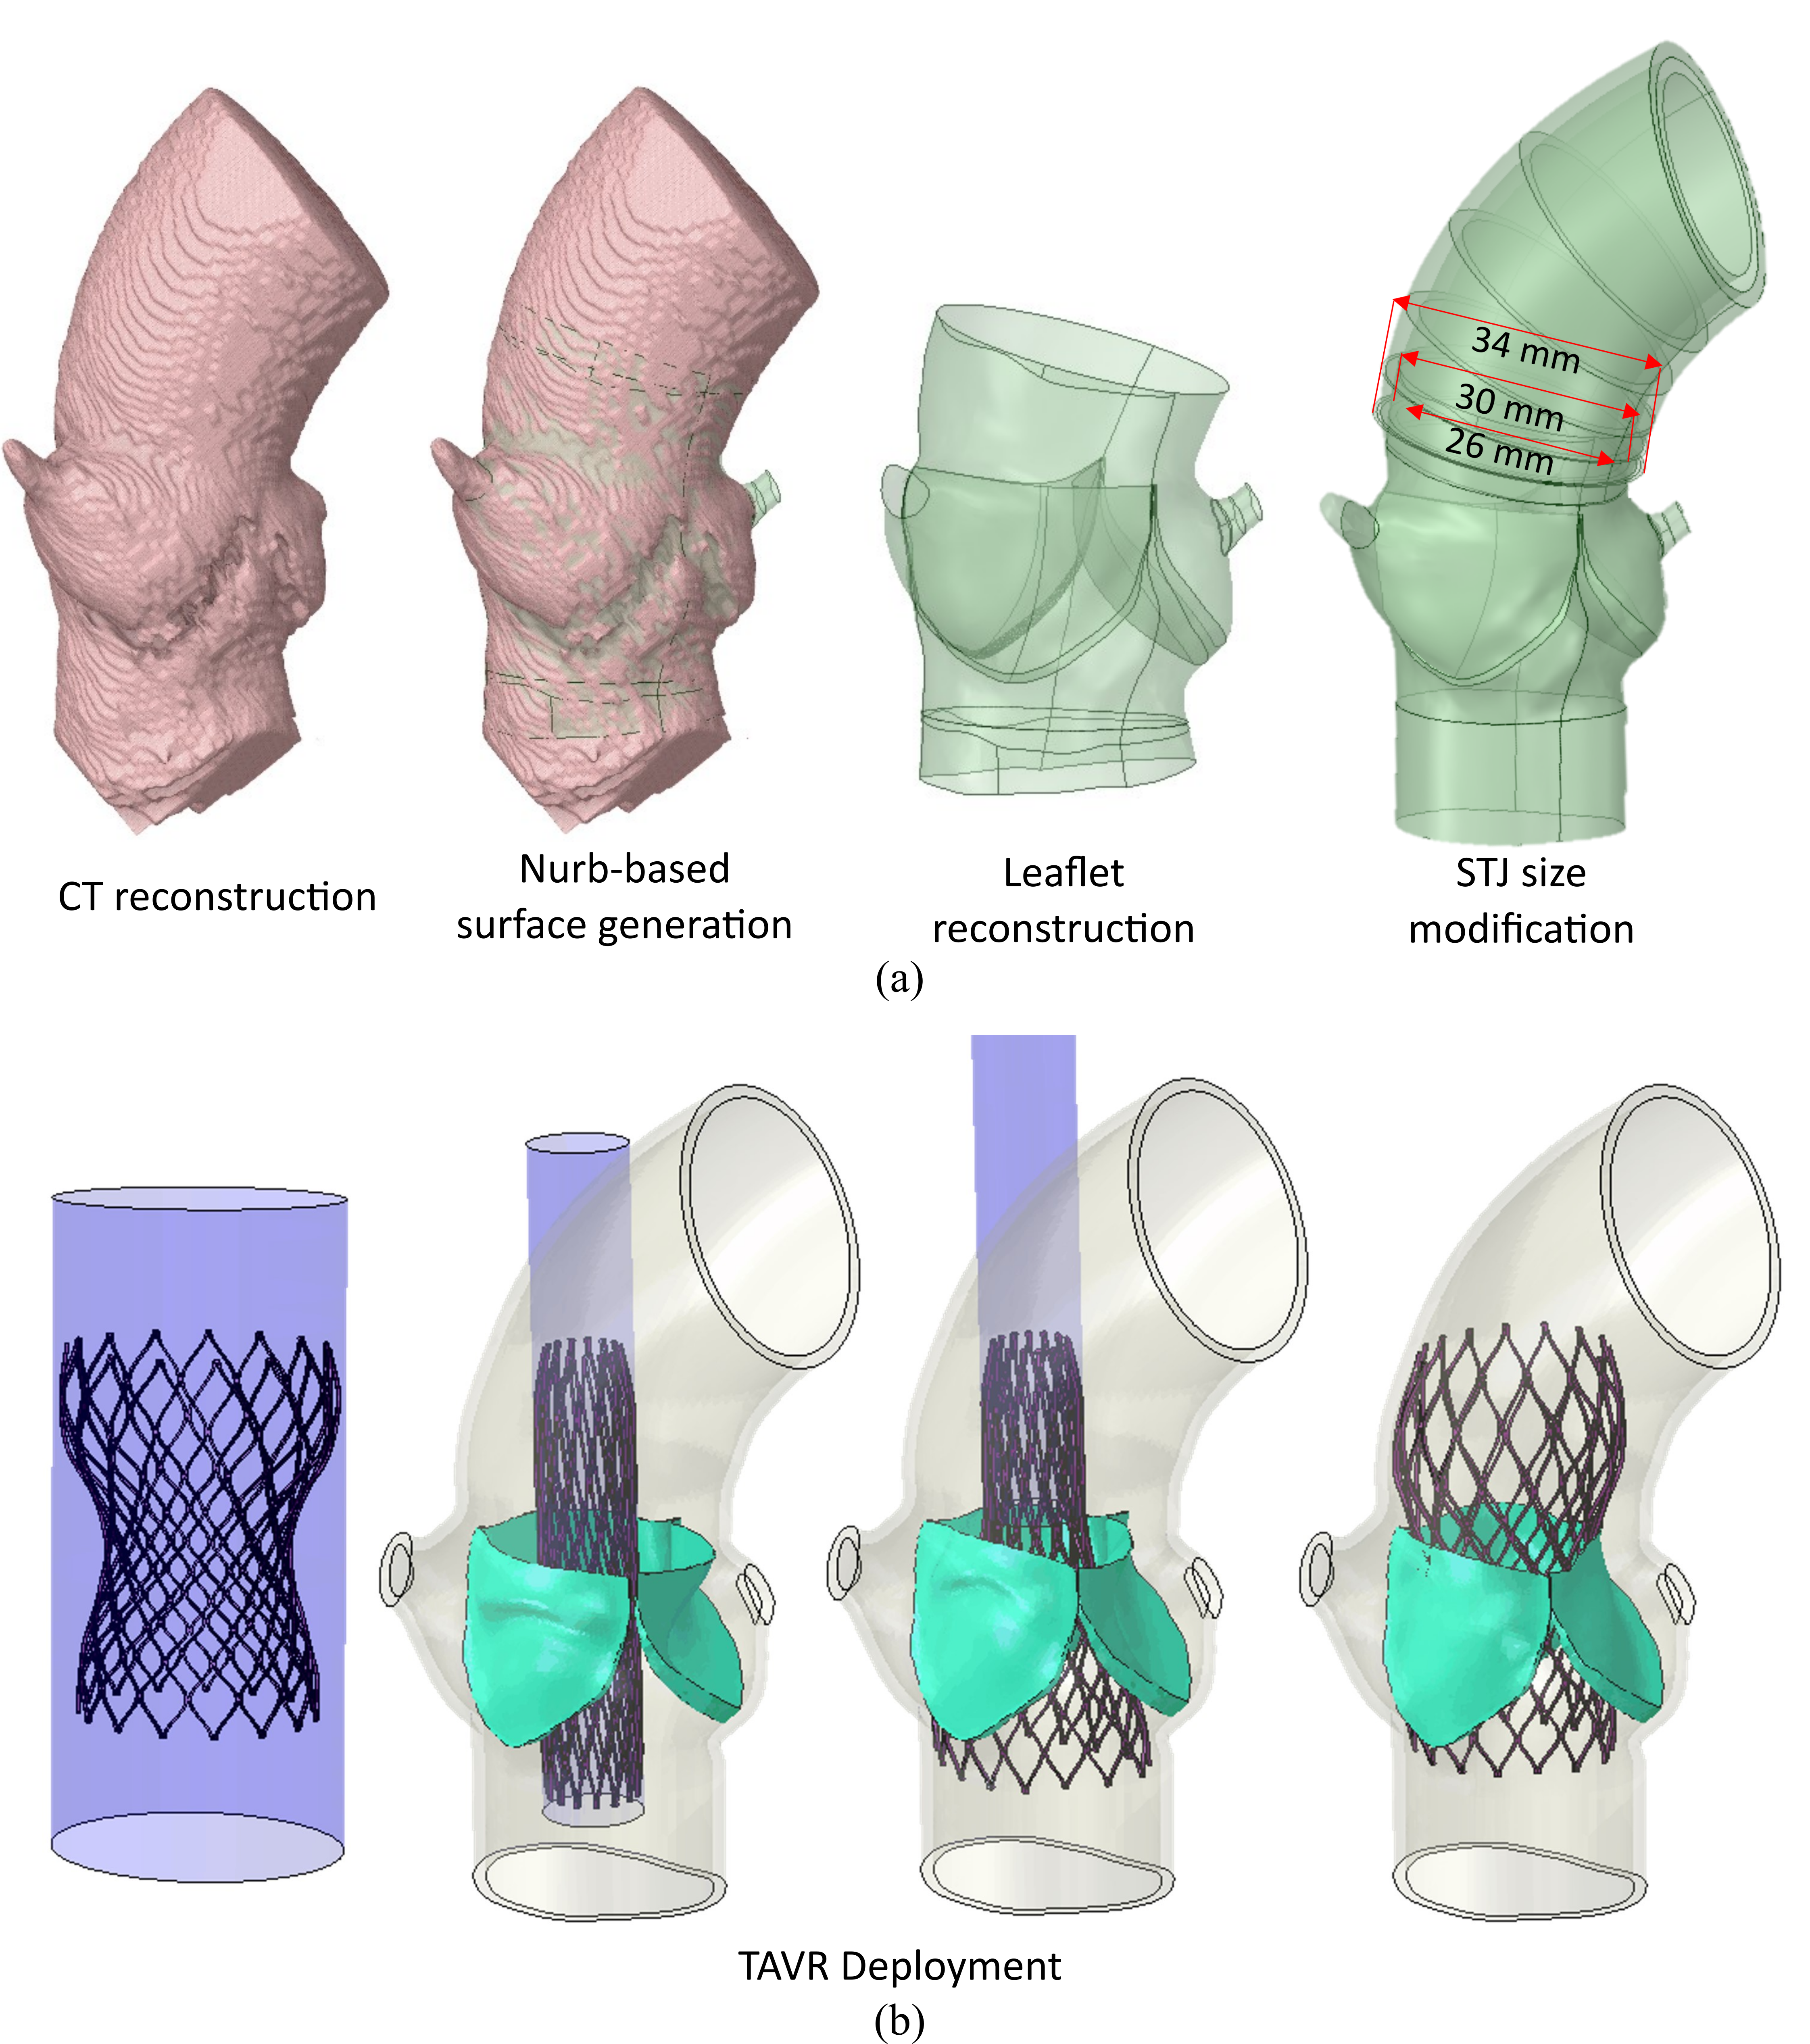

Effect of Sinotubular Junction Size on TAVR Leaflet Thrombosis

- TAVR has emerged as a standard approach for treating severe aortic stenosis patients. However, it is associated with several clinical complications, including subclinical leaflet thrombosis characterized by Hypoattenuated Leaflet Thickening (HALT). A rigorous analysis of TAVR device thrombogenicity considering anatomical variations is essential for estimating this risk.

- In this study, we presented a comprehensive framework to analyze structural analysis of TAVR deployment, hemodynamic analysis via FSI simulation coupled with thrombogenic risk assessment via Lagrangian particle tracking.

Patient model reconstruction and TAVR deployment

Patient model reconstruction and TAVR deployment

Structural analysis of device eccentricity

Hemodynamic analysis

- A smaller STJ size impairs adequate expansion of the TAVR stent, which may lead to suboptimal hemodynamic performance.

- Larger STJ size marginally enhances the hemodynamic performance but increases the risk of TAVR leaflet thrombosis. Such analysis can aid pre-procedural planning and minimize the risk of TAVR leaflet thrombosis.

Publication link- Effect of Sinotubular Junction Size on TAVR Leaflet Thrombosis: A Fluid–Structure Interaction Analysis